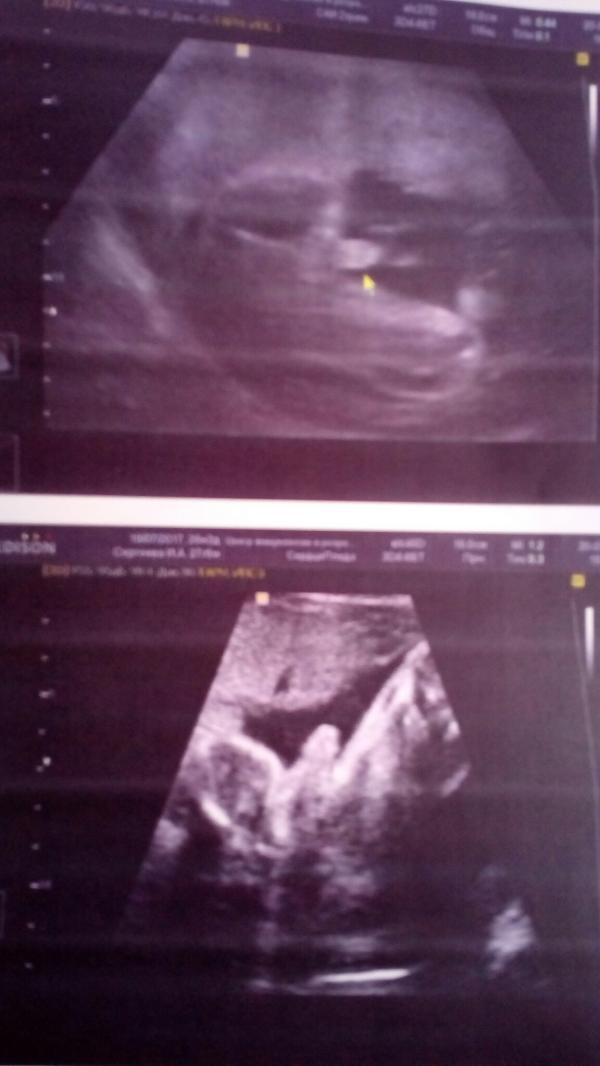

Сходили сегодня в ЦИР к Справцевой. Наконец-то мне не просто молча сделали УЗИ, а всё показали, рассказали, все органы, все части тела 😍😍😍

Парень у нас нескромный, показал всё, зевал лежал, глаза тёр, с пятками игрался. Муж в восторге ! Да и я тоже 😇 Заключение дали, 6 фоток распечатали (обычные и 3д). Главное, что здоров и всё развивается как и должно, по параметрам соответствует 26.4

Если думаете идти или нет, то обязательно сходите, эмоции потрясающие !